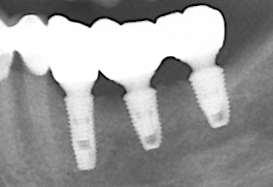

治療前X光片,骨頭嚴重吸收。